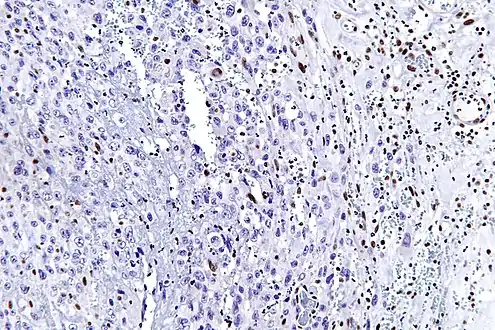

The most common genetic mutation (found in 80-90% of epithelioid sarcomas) is the inactivation of the SMARCB1 gene, or the loss of INI-1 function,[10][11] which is thought to be a major contributor to disease progression. Epithelioid sarcoma typically contains chromosome 22q11.2 mutations or deletions and 8q gains, particularly i(8) (>q10). Aberrations of 18q and 8q, as well as recurrent gains at 11q13, have also been observed.[12][13][14]

Tissue biopsy is the diagnostic modality of choice. Due to a high incidence of lymph node involvement, a sentinel lymph node biopsy is often performed. A common characteristic of epithelioid sarcoma (observed in 80% of all cases) is the loss of function of the SMARCB1 gene (also termed BAF47, INI1, or hSNF5). Immunohistochemical staining of INI1 is available and can be used for the diagnosis of epithelioid sarcoma. MRI is the diagnostic modality of choice for imaging prior to biopsy and pathologic diagnosis, with the primary role being the determination of anatomic boundaries.

High mag. (SMARCB1)